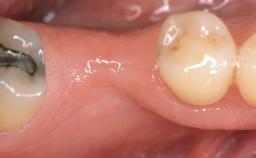

It is sometimes necessary to remove and replace compromised implants. This case is a clear example of the need for multiple steps to achieve an optimal therapeutic result for patients with non-salvageable implants. It illustrates how the lost soft and hard tissues were rebuilt in a sequence that improved the healing of the hard tissues and assured their long-term stability. The 35-year-old healthy patient presented with clinical attachment loss on the proximal and lingual surfaces of the natural dentition. Some gingival recession was present on natural teeth, particularly in the posterior sextants (S1, S3, S4, and S6).

Soft Tissue Anatomy Intact Defective

Bone Volume Horizontally and vertically sufficient Horizontally deficient Deficient vertically or deficient vertically AND horizontally